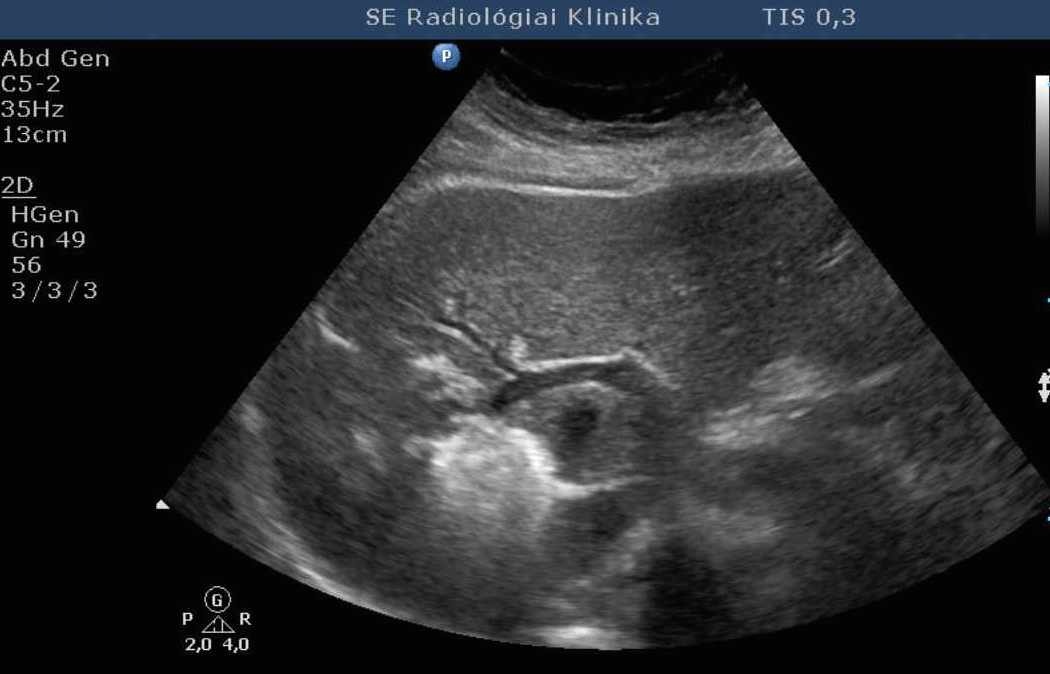

Compared to the surgical methods of past, nowadays these cystic lesions can be successfully treated percutaneously with alcoholic cyst sclerotization. (Figures 26., 27.).

Image

Figure 26. – Percutaneous ethanol cyst sclerotization ( filling up of the cyst before the sclerotization)

Figure 27. – US and CT examinations before percutaneous ethanol sclerotization (A: US examination, B: CT examination)

The puncture of the cyst is usually guided with US (rarely with CT). The puncturing needs to take place from the parenchymal side of the cyst. When its contents are removed the empty cavity is filled up with diluted contrast material to ensure that there is no contrast leakage to the surroundings. The 96% ethanol is only injected after the contrast material has been removed and no leakage was found. (The volume of the alcohol should not exceed 50-60% of the cyst or 100 ml.)

The injected ethanol is left in the cyst for 20 minutes. Following this, the alcohol is drained as well. Cystic regression is then regularly controlled with US or CT examinations. (Figures 28., 29.) Patient complaints usually cease within 4-6 weeks after the treatment.